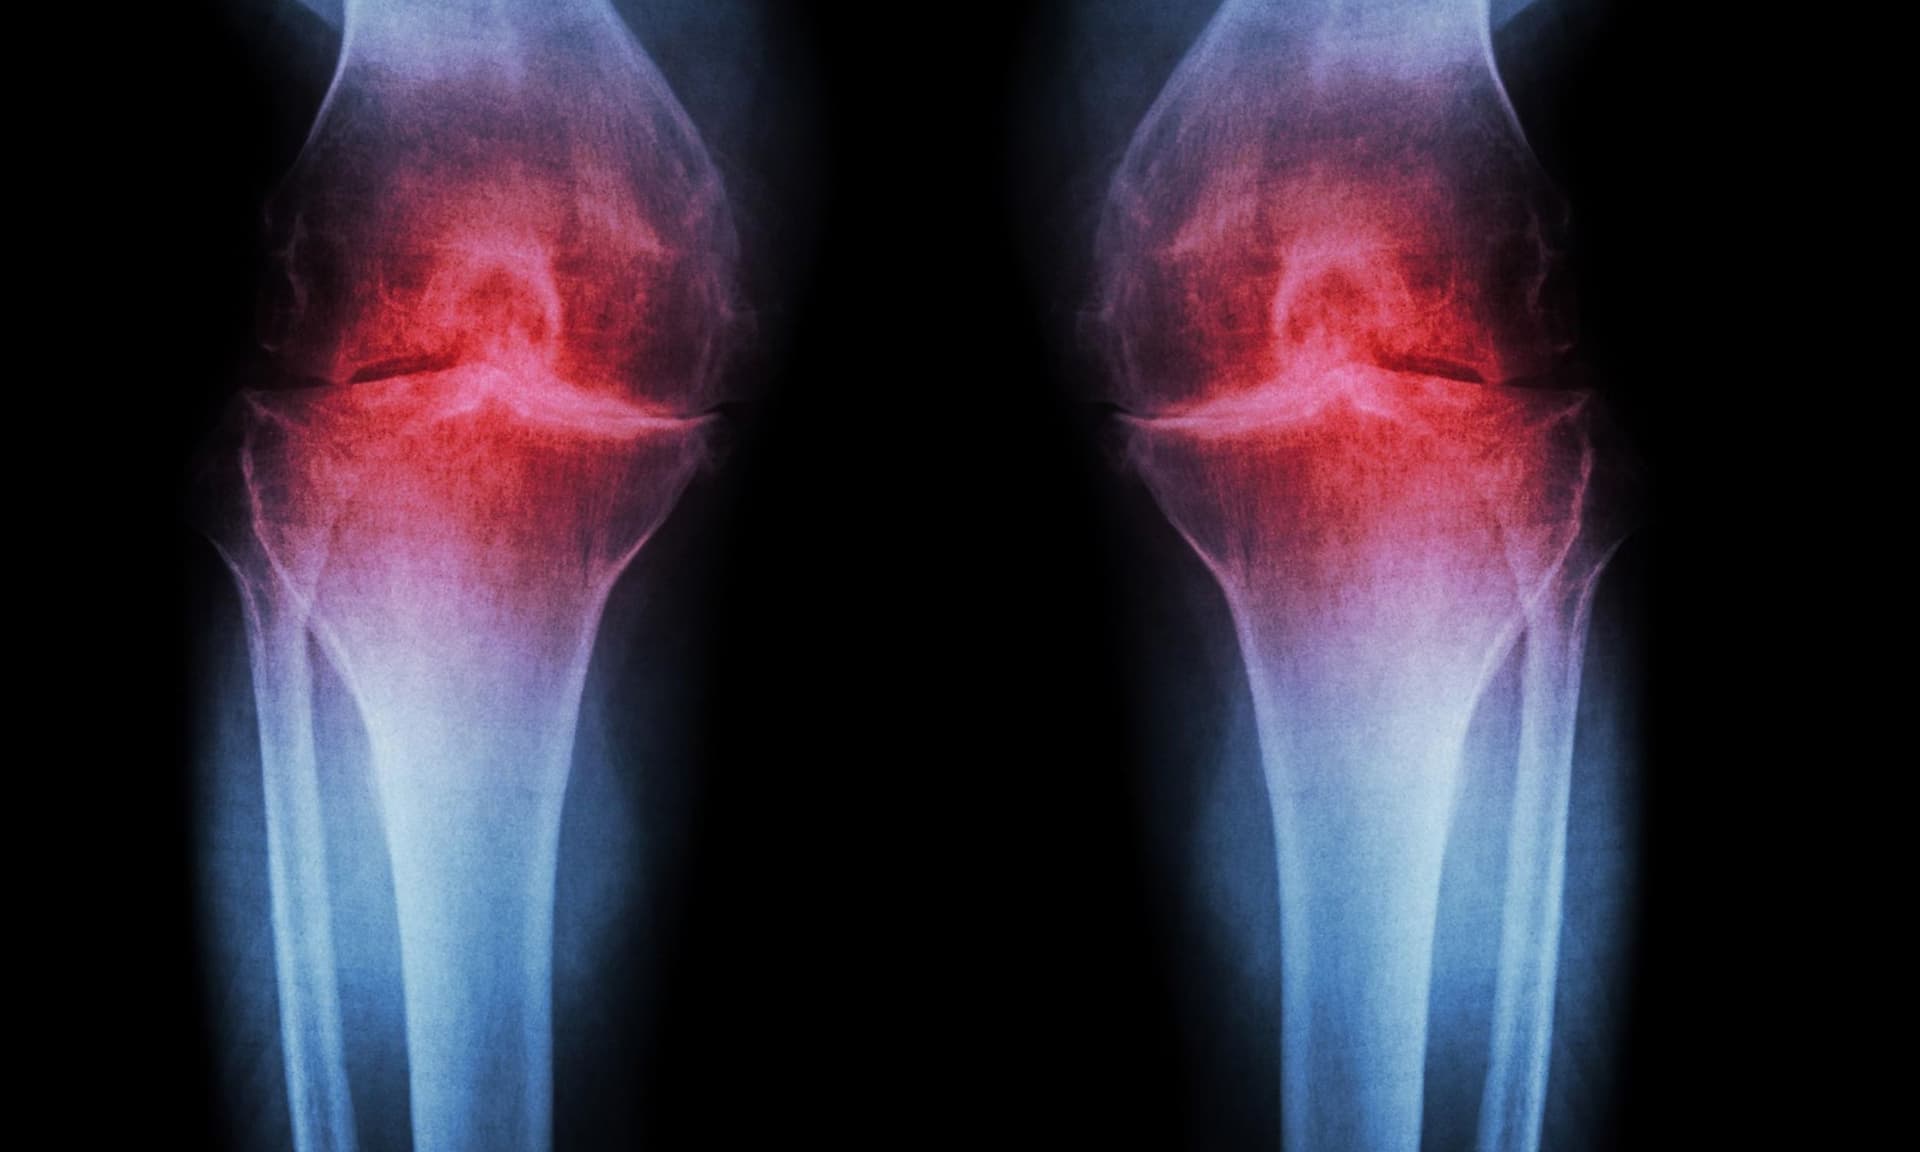

Scientists restore knee cartilage using targeted injection

Scientists have developed an experimental inhibitor that successfully regenerated knee cartilage in aged mice, offering a potential alternative to arthritis and prosthetics. The inhibitor, which blocks an age-linked protein, led to cartilage regrowth in mice even when they were already old. Human knee tissue exposed to the same blocker also showed signs of new cartilage formation. The study suggests that this approach could provide a new treatment option for knee osteoarthritis, which affects about one in five adults in the United States and leads to significant direct medical costs. The research, published in Science, highlights the potential of targeted injections to delay joint replacement and improve quality of life for those suffering from knee-related issues.